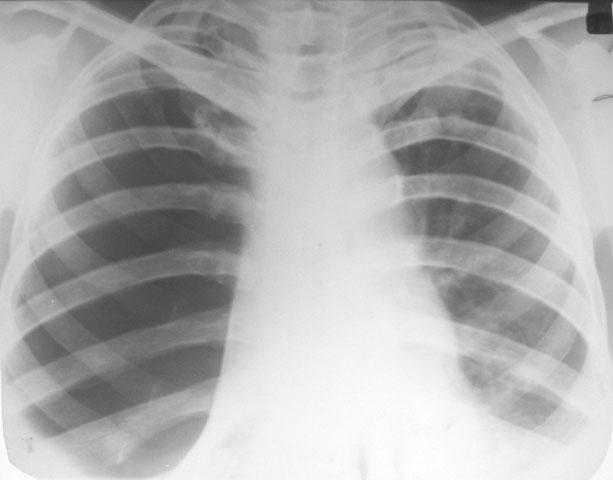

Рентгенологические изображения и синдромы патологии легких

Раздел: Кадры-подсказки